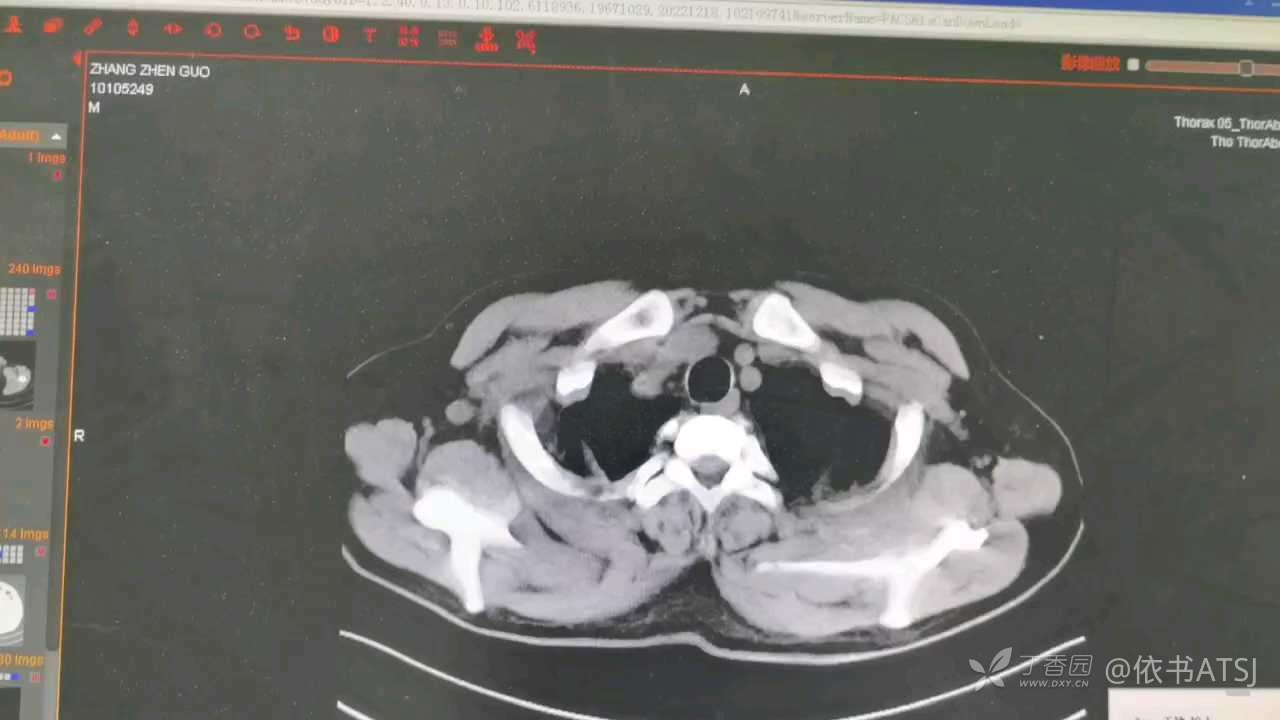

xiaospring 推荐患者一:59岁,尿毒症患者浑身疼痛,新冠阳性,胸腹部CT提示主动脉弓→腹主动脉(髂总动脉开口处)夹层破裂,病情凶险~

主动脉弓降主动脉密度不均,约至髂总动脉分叉处,部分呈双腔征,幸好值班医生重视了,排查及时,不然死了还不知啥原因。